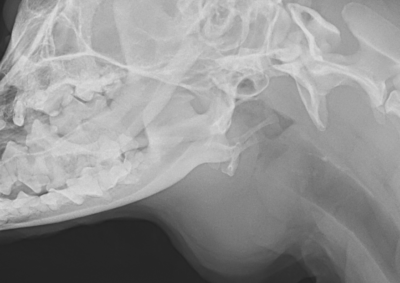

軟部組織外科 注意 ボタンをクリックした先に、治療中および手術中の画像が説明で使用されている場合がございます。 そのような画像に弱い方は閲覧なさらないようお願いいたします。 軟部組織外科 犬の唾液腺切除 軟部組織外科救急・集中治療 猫の腸重積 軟部組織外科呼吸器外科 複数の肺葉捻転 軟部組織外科 肝臓・脾臓過形成病変 軟部組織外科 胆嚢粘液嚢腫 軟部組織外科 尿道狭窄に対する経骨盤尿道瘻設置術 軟部組織外科救急・集中治療 猫の両側尿管閉塞 軟部組織外科救急・集中治療 猫の腸閉塞(毛玉) 軟部組織外科 唾液腺嚢胞 軟部組織外科腫瘍外科 断脚手術(軟部組織肉腫) 軟部組織外科腫瘍外科 猫の肝葉切除術(内側左葉) 軟部組織外科救急・集中治療 腸閉塞・腸切開 <12345678> 症例カテゴリー 放射線治療整形外科軟部組織外科脳神経外科内科腫瘍外科救急・集中治療リハビリテーション科腫瘍内科内視鏡科脳神経科呼吸器外科中医・漢方猫の腎移植循環器科